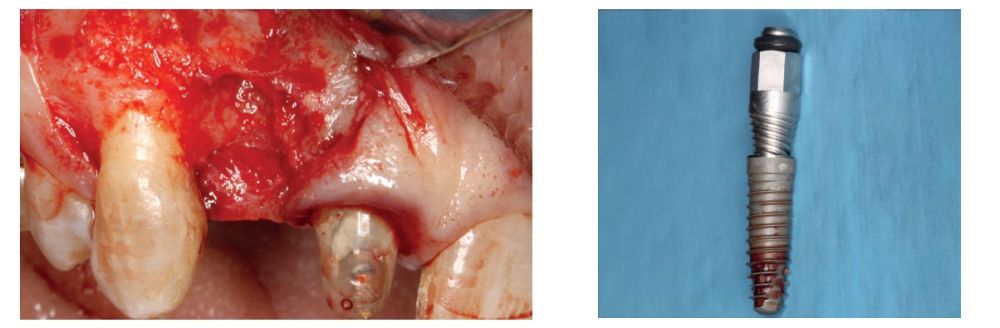

We present the case of a 36-year-old woman who comes to the clinic demanding solution for an implant located in position 1.2. This implant has carried a rehabilitation with a crown for a short period of time in which an important mucositis and loss of the thickness of the gingival tissue occurred, for which the crown was removed. The patient has a provisional removable crown and the soft tissue surrounding the area of the initial emergency of the implant-supported prosthesis is in bad condition, with a significant loss of thickness and the remains of a soft tissue fistula (Figures 1-4).

To continue with the study of the case, a Cone Beam is performed where we can observe three-dimensionally the position of the implant located in position 1.2. In the sectional cuts it is visualized completely positioned toward vestibular with an almost complete resorption of the cortical bone of this area, which explains the underlying soft tissue problems. The periapical radiography shows the position of the implant with respect to adjacent teeth (Figures 5 and 6). With this image we proceed to create a flap and the explantation of the implant. The crown located in tooth 1.1 is also removed to be able to make another crown that will serve to support the provisional extension for zone 1.2, while the first procedure heals. In this first approach a block grafting obtained from the mandibular ramus is also placed which is fixed with a microscrew in the area to be regenerated where the vestibular cortical has been lost. Once fixed and positioned, it is filled around the block grafting with particulate bone obtained with a bone-scraper of the same donor zone embedded in PRGF-Endoret for better fixation and cellular viability (Figures 7-9).